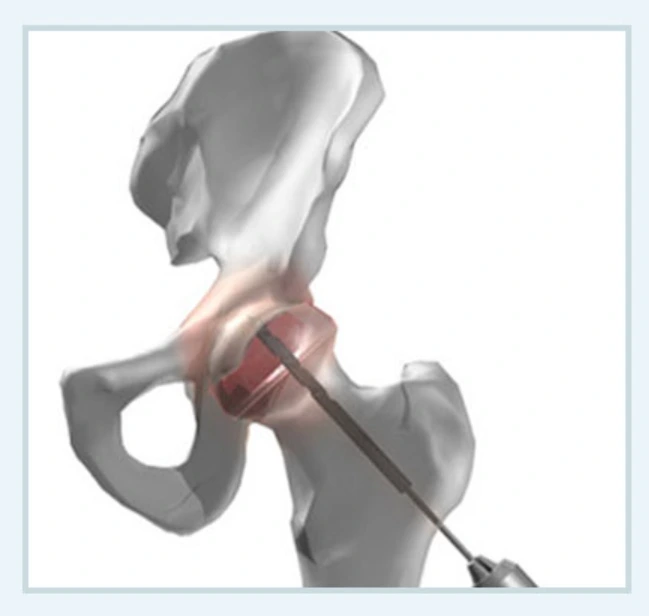

다발성 천공술

비교적 간단한 수술로 대퇴골두무혈성괴사 초기에 시행하는 수술입니다. 대퇴골두에 구멍을 뚫어서 대퇴골두의 내압을 낮추는 방식이지요. 작은 구멍만으로 치료를 하기 때문에 흉터에 대한 걱정은 하지 않아도 된답니다.